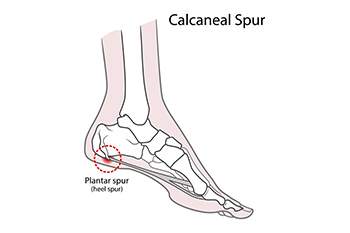

How Are Heel Spurs Treated?

A heel spur is also known as a calcaneal spur and is a bony growth formed by calcium deposits on the underside of the foot. They can have a pointy, hooked, or shelf-like shape. Heel spurs are the body’s way of trying to protect the foot from another foot condition, such as plantar fasciitis. Heel spurs can also arise from arthritis, overuse, obesity, and improper footwear. These growths do not always cause pain but when they do, the heel can be tender, with dull or sharp pain when standing. Usually, it is the underlying condition that causes the pain. Women are more likely to get heel spurs than men. A diagnosis will consist of a visual examination of the foot and understanding where the pain arises with movement, as well as an X-ray, which will highlight the bony growth. If you have a heel spur that is causing you discomfort, it is suggested that you make an appointment with a podiatrist to discuss treatment options of the spur itself or the underlying condition which may be causing it.

Heels Spurs

Heel spurs are formed by calcium deposits on the back of the foot where the heel is. This can also be caused by small fragments of bone breaking off one section of the foot, attaching onto the back of the foot. Heel spurs can also be bone growth on the back of the foot and may grow in the direction of the arch of the foot.

Older individuals usually suffer from heel spurs and pain sometimes intensifies with age. One of the main condition's spurs are related to is plantar fasciitis.

Pain

The pain associated with spurs is often because of weight placed on the feet. When someone is walking, their entire weight is concentrated on the feet. Bone spurs then have the tendency to affect other bones and tissues around the foot. As the pain continues, the feet will become tender and sensitive over time.

Treatments

There are many ways to treat heel spurs. If one is suffering from heel spurs in conjunction with pain, there are several methods for healing. Medication, surgery, and herbal care are some options.

How to Treat Heel Spurs

Heel spurs are calcium deposits that cause bone protrusions on the heel bone. Heel spurs are usually associated with plantar fasciitis, which occurs when the plantar fasciitis in the foot becomes inflamed. Typically, heel spurs don’t cause any symptoms. However, they can produce chronic or intermittent heel pain. Those who have had the condition often describe the irritation as a stabbing pain.

There are risk factors that may make you more likely to develop heel spurs. People who have abnormal walking gaits, run and jog on hard surfaces, are obese, or wear poorly fitting shoes are more likely to develop heel spurs.

Fortunately, there are precautions you can take to avoid developing heel spurs. One of the best ways to do this is by wearing well-fitting shoes with shock-absorbent soles. Another preventative technique is to choose running shoes if you plan on running, and walking shoes if you plan on walking. Shoes are made for different activities and it is important to research a shoe before you purchase a pair.

The pain associated with heel spurs often decreases the more you walk. However, a recurrence of pain after an extended period of rest or walking is likely to occur with this condition. Those with severe heel spur pain may opt to go the surgical route for treatment. However, more than 90% of those with the condition get better without surgical treatment. If you have a heel spur and want to know if surgery is right for you, you should go to your podiatrist and he or she will be able to conduct a pre-surgical test or exam to determine if you are an optimal candidate for surgery.